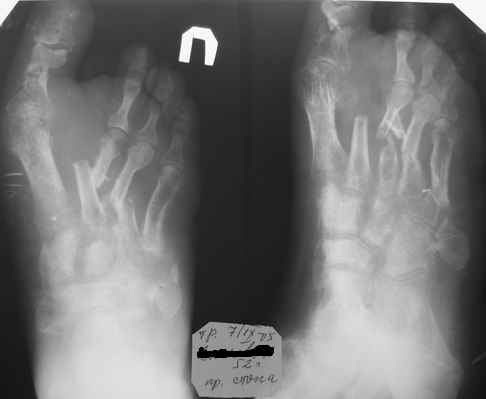

Уважаемые коллеги! Мужчина 51 год, 23 апреля 2005 года на стопу упала мет. балка. Получил открытые переломы плюсневых костей.

При поступлении ПХО, гипсовая лонгета, на следующий день множественные фликтены. Стабилизация в АВФ на третий день. В дальнейшем, по всей видимости, компартмент синдром с некрозом участка кожи на тыле стопы. Проводились этапные некрэктомии, в т. ч. дезартикуляция второго пальца. К сожалению, в силу сложившихся обстоятельств, пациент побывал в руках не единственного хирурга (не отрицаю в первую очередь своих). Дальнейшее лечение - консервативное, направленное на заживление раны. Аппарат демонтирован через 3 месяца. Сейчас ходит с небольшой нагрузкой. Прошу указать на допущенные по Вашему мнению тактические ошибки и дать советы по дальнейшему ведению больного. С уважением, А.Минервин. О себе: Минервин Алексей, заведующий травматологическим отделением ГБ 3 г. Муром, Владимирской области.

Дальнейшее ведение Вашего пациента, по моему мнению, должно свестись к коррекции возникших биомеханических нарушений функции стопы, в отдельных случаях удается обойтись ортопедическими стельками или подбором специальной обуви, при условии что представленный Вами снимок не последний и положение отломков все- таки стало лучше.

Если же последний снимок с таким положением отломков, то больному в дальнейшем показана коррегирующая операция. Открытая репозиция, при необходимости остеотомии и фиксация пластинами,либо фиксация в аппарате. Любая методика должна быть направлена на восстановление свода стопы и ее амортизирующей функции.

Здравствуйте, Тимур Вячеславович. ".случай действительно тяжелый, и результат по видимому будет не плохой"(?) Опечатка (не очень хороший?). Снимок самый свежий- 2-х недельной давности-тот, что самый левый в строке. Вопроса два. 1)ориентировочные сроки выполнения корригирующих операций в данном случае; 2)куда можно направить больного с учетом нашего региона (случай неординарный для лечения в районе).